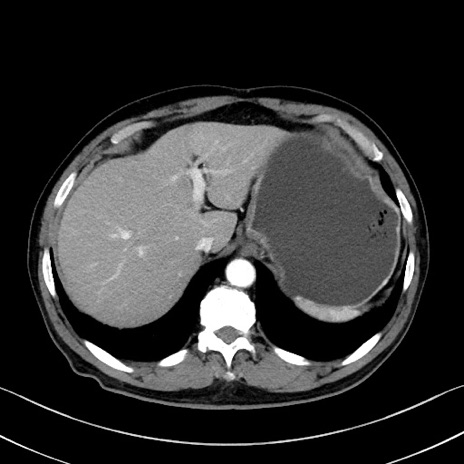

症例35(横断像)

【症例】70歳代 男性

【主訴】腹部膨満、嘔吐

【現病歴】昨日より腹部膨満感出現。本日増悪し、仙痛出現。嘔吐あり、受診。

【既往歴】糖尿病、胆摘後

【身体所見】BP 149/80mmHg、HR 74/min、BT 35.9℃、腹部:膨満、軟、圧痛なし。腸雑音減弱あり。上腹部正中切開瘢痕あり。

【データ】WBC 13500、CRP 1.72